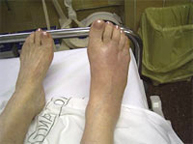

Las potentes estructuras ligamentosas que unen los huesos del pie hacen que su ruptura sólo obedezca a traumatismos de muy alta energía como accidentes de tráfico o caídas desde gran altura. La separación entre los huesos de una articulación del pie de forma traumática produce una gran inflamación y dolor que impide caminar. Debido a la tumefacción y dolor la exploración física es difícil por lo que la radiología y la tomografía computerizada nos ayudarán a realizar un diagnóstico preciso. El tratamiento dependeráde la estabilidad de la lesión. Debe conseguirse la restitución y mantenimiento de la anatomía fisiológica del pié lo antes posible para disminuir el proceso inflamatorio y disminuir las potenciales secuelas que se puedan derivar de esta lesión.Son típicas de la segunda y tercera década de la vida y afectan casi siempre al sexo masculino por su mayor predisposición a los deportes de velocidad (motociclismo, automovilismo, ciclismo, esquí) y de contacto (karate, judo, tae-kwon-do).